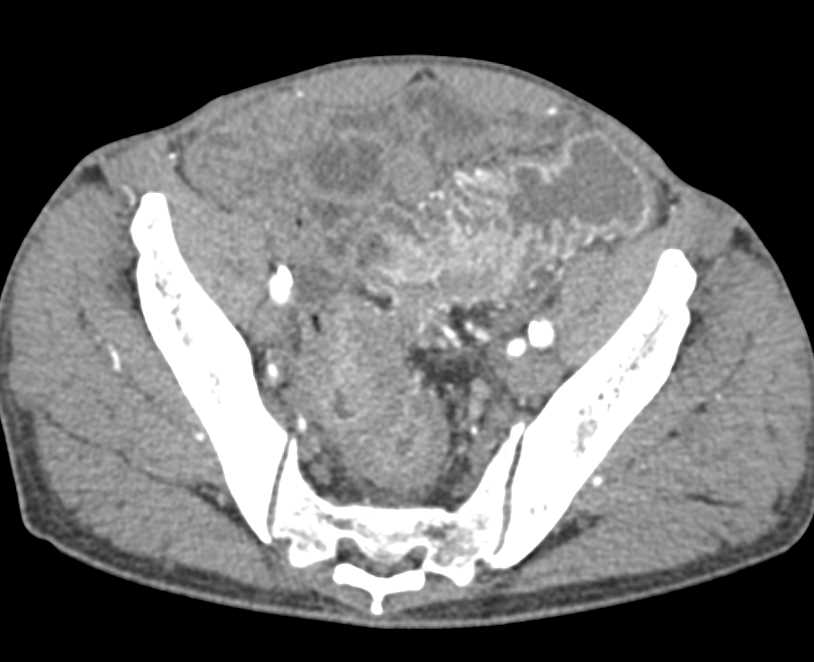

Mucocele of the Appendix